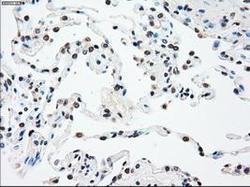

Immunohistochemistry

GTX83560 IHC

Full details

Method: